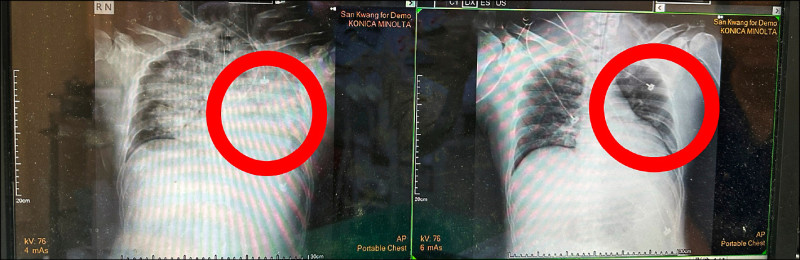

衛生福利部豐原醫院副院長張正一表示,張男到院檢查,發現雙側肺部出現大片浸潤,顯示已處於嚴重缺氧狀態,同時檢查出腦血管瘤破裂,併發大範圍顱內出血及顱內壓急劇升高,屬於同時危及腦部與呼吸循環的高致命風險個案。

張正一說,醫療團隊立即執行腦室外引流手術,成功降低顱內壓,為腦部爭取關鍵存活時間,但術後患者仍持續嚴重缺氧,因急性呼吸窘迫,隨即由心臟血管外科醫師胡家瑜啟動ECMO(葉克膜)治療,暫時取代心肺功能,使氧合與血流狀況得以穩定,成功撐過最危險階段,患者於住院第4天順利脫離葉克膜,第21天成功脫離呼吸器,目前已返家休養,持續接受後續復健治療。